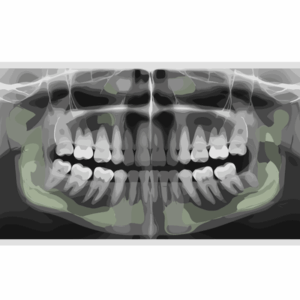

At Cleveland Smile Center, we use advanced CBCT imaging technology to carefully evaluate your bone structure and create a precise treatment plan tailored to your specific needs. This advanced planning helps ensure the best possible outcome for your implant procedure.